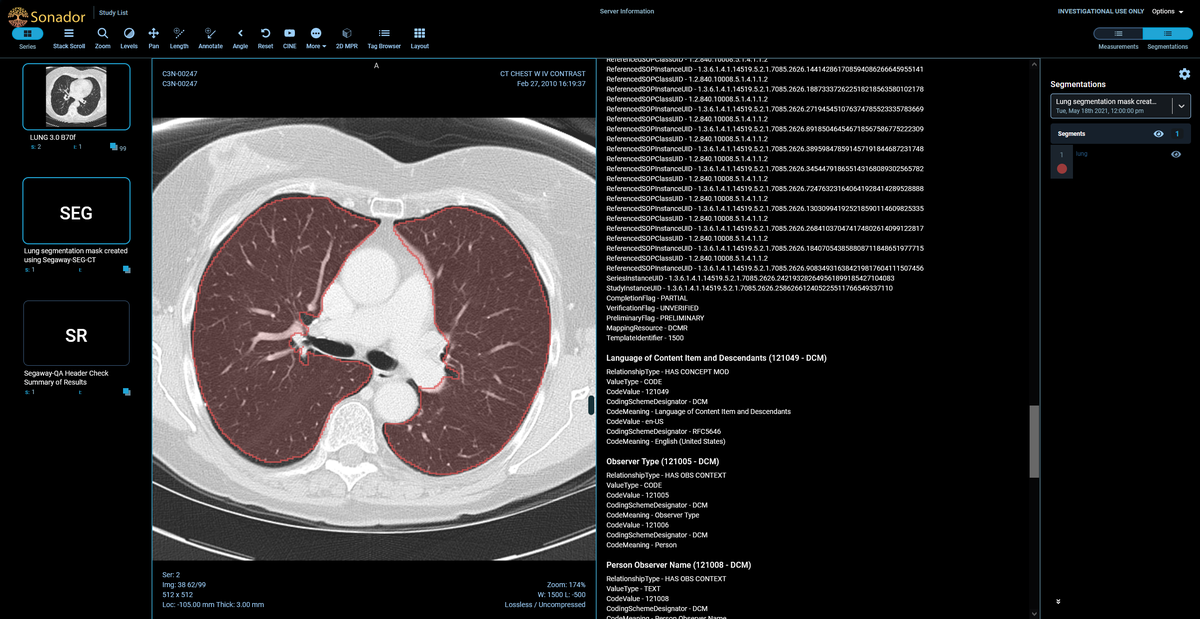

Once you have completed all instructions in the notebook, you can view the example CT study by opening http://imaging.local:8070 in your browser (or refreshing the page if you already have it open) and clicking on the C3N ... row in the "Study List."

- Exploring other notebooks in the examples repository to see how technologies such as DICOM-SR can be used alongside Orthanc for integrating AI applications with other systems (such as Radiology Information Systems or Electronic Medical Records) or how AI applications can be built on top of Sonador.